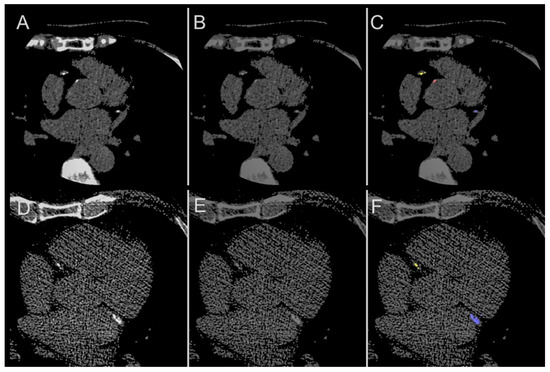

| Structure | Category | Dice Score | ||

|---|---|---|---|---|

| Median | Quartile (1st, 3rd) | p | ||

| Total coronary (LAD + RCA + LCx) | Overall | 0.952 | (0.921, 0.981) | - |

| Aortic | Overall | 0.832 | (0.759, 0.897) | |

| Male | 0.802 | (0.760, 0.905) | 0.996 | |

| Female | 0.834 | (0.764, 0.883) | ||

| Age < 65 years | 0.833 | (0.776, 0.933) | 0.204 | |

| Age ≥ 65 years | 0.793 | (0.756, 0.862) | ||